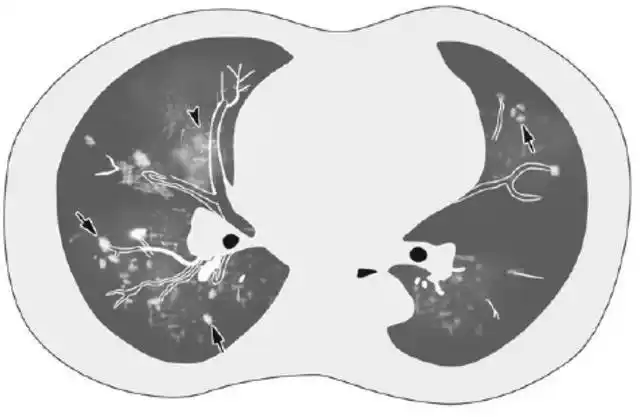

空洞形成 小叶性干酪样肺炎